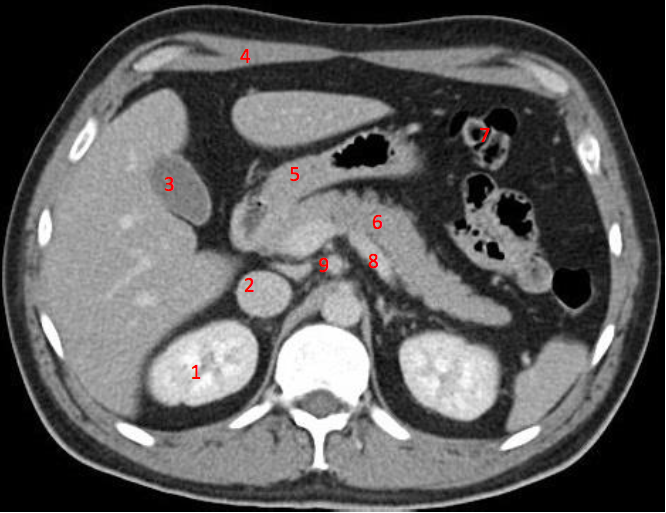

Number 3?

IVC

Number 1?

R Kidney

Number 2?

Gall bladder

Number 8?

Body of thoracic vertebra

Number 4?

Rectus abdominus

Descending colon

Number 7?

Bowel (probably large)

Number 6?

Stomach

Number 5?

Rt ureter

Number 9?

Superior mesenteric artery